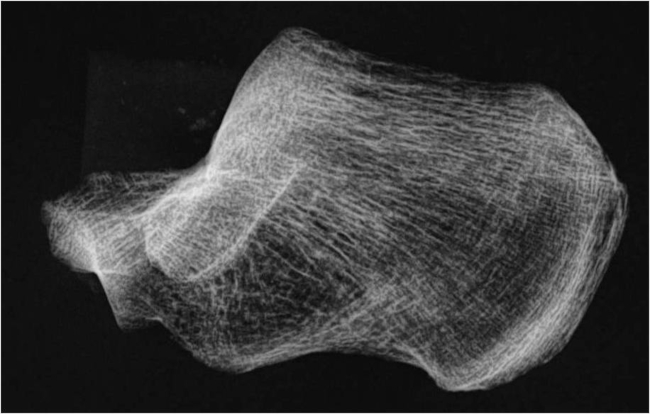

Fase II (osteoporosis): El grupo tensil secundario desaparece y el primario se reduce aún más.

Fase I (osteoporosis severa): Desaparecen ambos grupos tensiles. Las trabéculas de compresión se adelgazan y reducen en número (►Fig. 4).